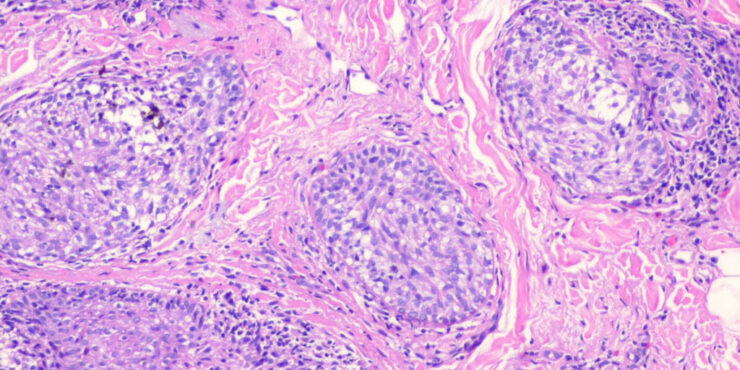

Read MoreCutaneous lymphadenoma =الغدوم اللمفاوي الجلدي